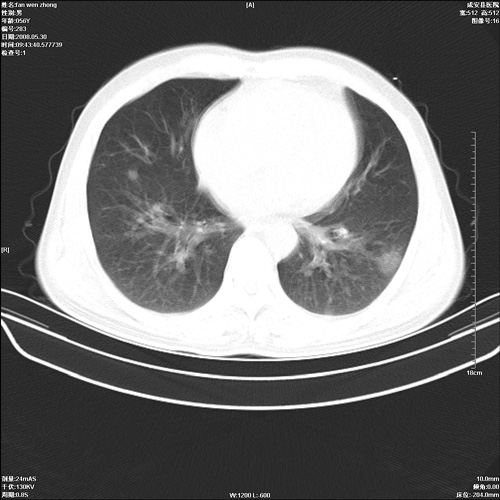

病人 男 56岁 一周前高热,体温达39-40度,经抗炎治疗后,体温渐降,达37,5-38度,轻微咳嗽,胸部不适 查白细胞为1.3万 行ct检查,请分析。

双肺内可见多发结节状病灶,并见小空洞,病人高热,白血球增高,应该是典型的迁徙性肺脓肿(多为金黄色葡萄球菌感染)。查一下口腔等其它部位有无感染灶。

双肺内可见多发结节状病灶,并见小空洞,病人高热,白血球增高,应该是典型的迁徙性肺脓肿(多为金黄色葡萄球菌感染)。建议治疗后复查.